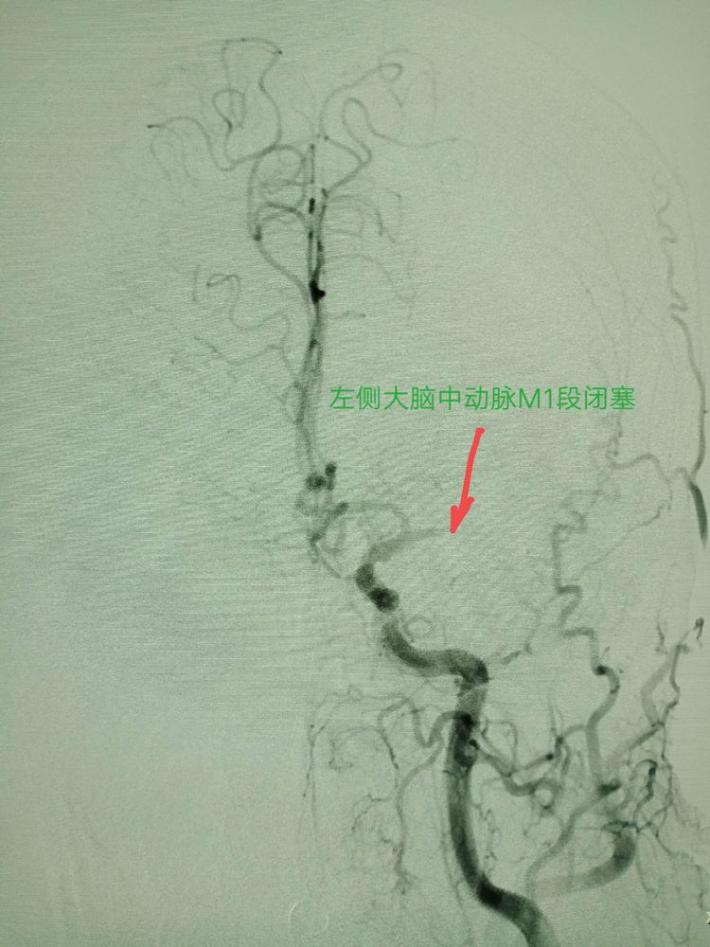

左侧颈总动脉造影提示:左侧大脑中动脉闭塞,考虑责任病变。

取栓后五分钟,血流减慢,难以维持,左侧大脑中动脉M1段原位狭窄。